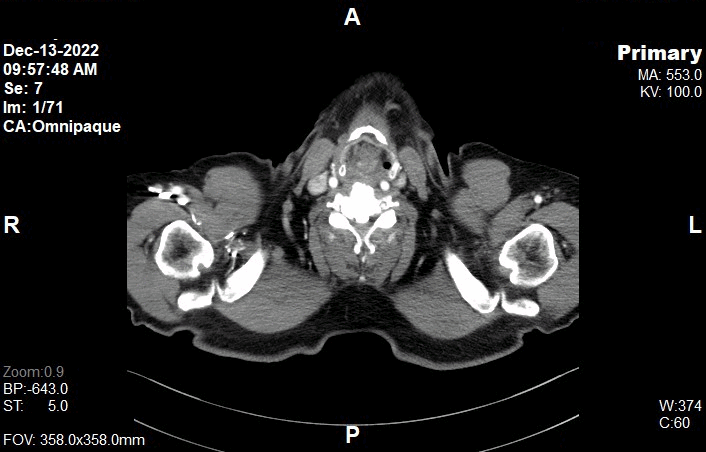

Appearance of CT Thorax Images

• kV: 100 kV

• Slice: 5.0mm